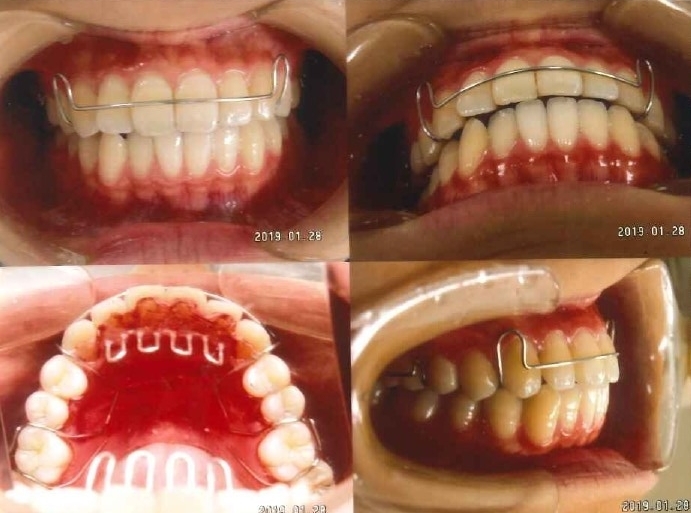

ケース2

-

治療前

-

治療後